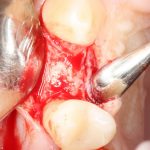

Разрез и скелетирование альвеолярного гребня.

Разрез и скелетирование делаются, исходя из двух взаимоисключающих нюансов: с одной стороны, разрез должен быть минимально травматичным, с другой — обеспечивать хороший обзор:

Мы немного смещаем разрез в сторону нёба для того, чтобы потом нормально сформировать десну. Это видно на правой фотографии выше.

Затем рана скелетируется, открывается кость верхней челюсти:

Поскольку ранее мы сделали и внимательно изучили компьютерную томографию, то для нас никаких неожиданностей на этом этапе нет и быть не может. Мы спокойно приступаем к подготовке лунки под имплантат.